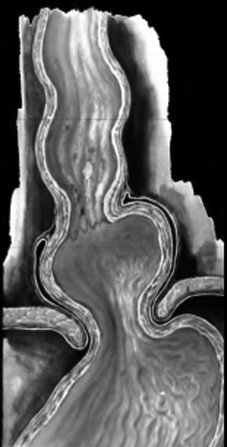

Hernie hiatale type I ( hernie hyatale de

glissement ) |

Image radiologique TOGD

une hernie hiatale de type glissement ( Type I ) ,

Le cardia glisse a travers hiatus diapragmatique

avec une partie de estomac |